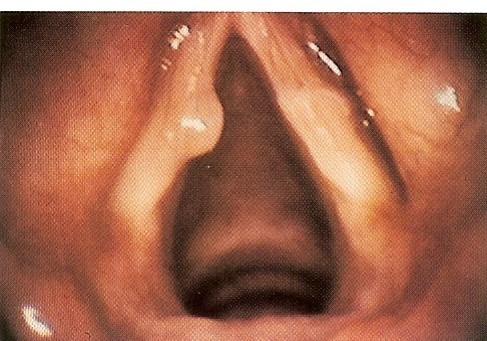

What is this?

Soft Nodule

Stroboscopic Characteristic:

vocal fold nodule

Polyp